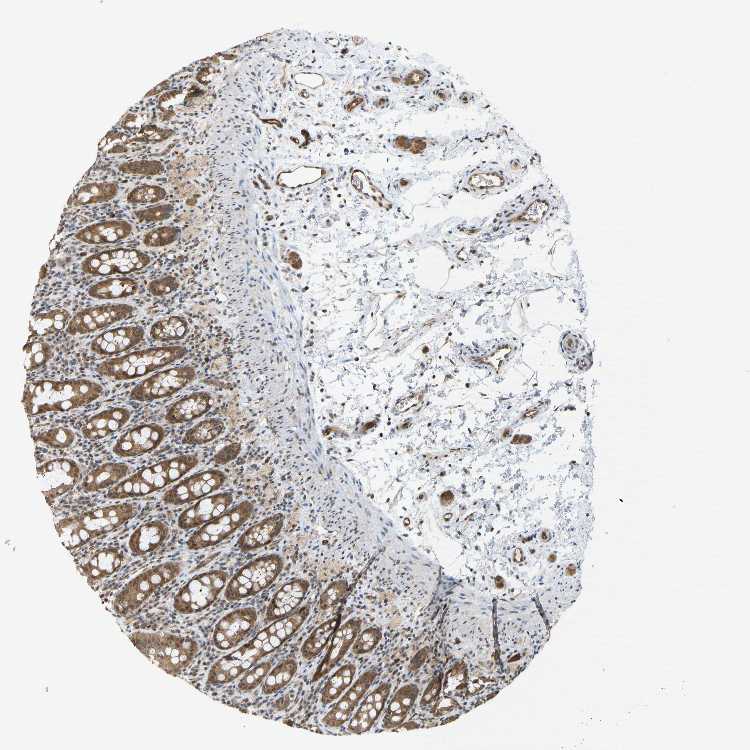

CCT8